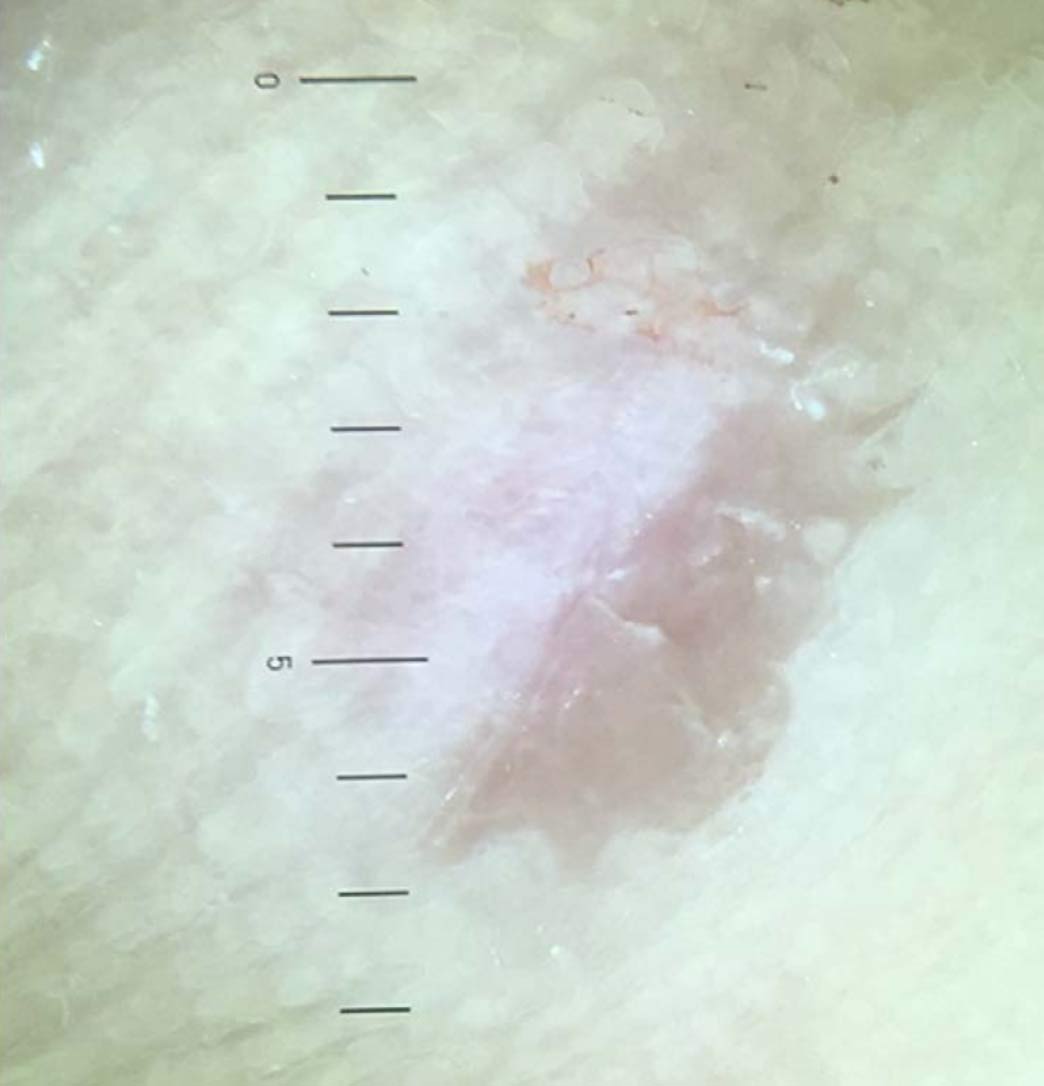

Figure 1. Dermoscopy of a debrided plantar wart showing a frog spawn like appearance with white halos, with capillaries at the center of the lesion.

In recent years, the use of dermoscopy has increased in the assessment and recognition of skin lesions. Dermatoscopic evaluation of the visual features of warts has been undertaken. Observable reported features in warts include the presence of dots and globules—these can be red, brown, or black in color and probably represent dilated capillaries. These capillaries are situated at the center of white halos giving a frog spawn like appearance (Figure 1). In some lesions, abrupt interruption of the natural dermatoglyphics is easily observable under the polarized light of the dermatoscope. Callus, a common differential diagnosis on the sole, lacks the typical dots and globules seen in warts whilst there is no interruption in the natural dermatoglyphics (Figure 2). In addition, callus displays central reddish to bluish structureless pigmentation.